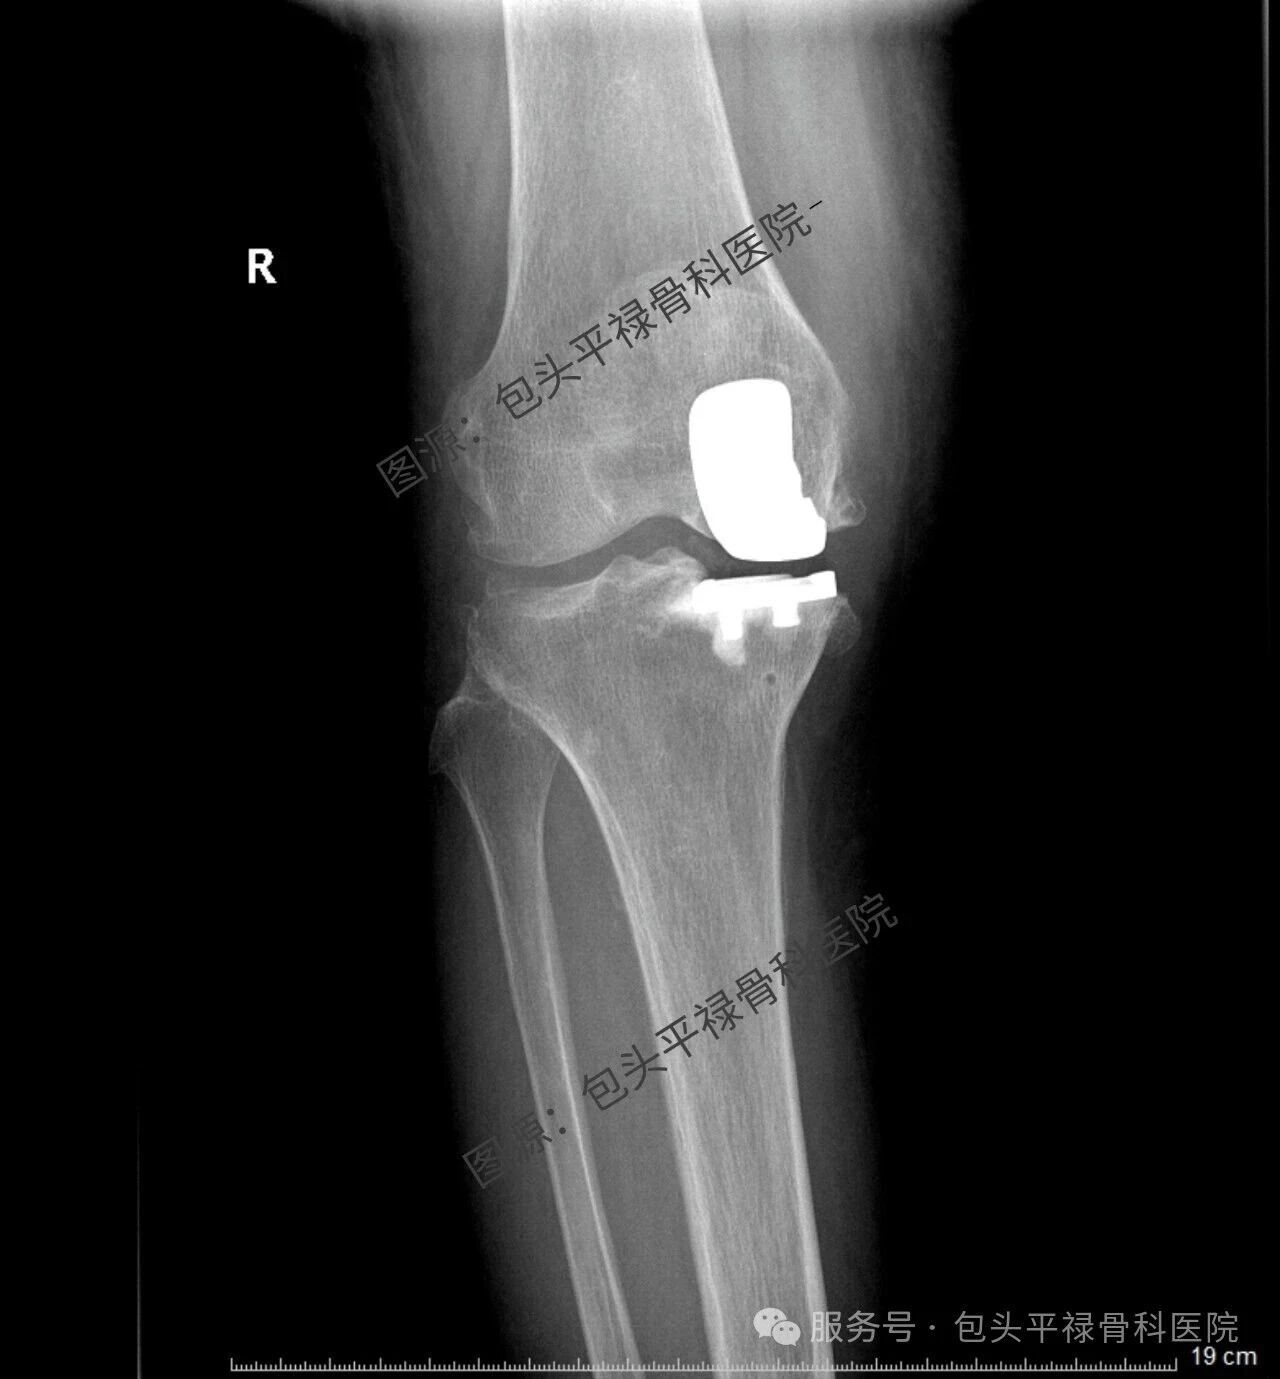

其实,现代医疗技术日趋精准,如果患者的关节炎只局限于膝关节的一个部分(单侧间室),那么TA很可能适合一种更为精准、创伤更小的手术——膝关节单髁置换术。

膝关节单髁置换术相当于“局部翻新”,就是只置换“坏掉房间”的磨损表面,仅将受损的软骨和部分骨质去除,替换为人工假体,而完好的软骨、交叉韧带及其他结构都得以最大程度的保留。